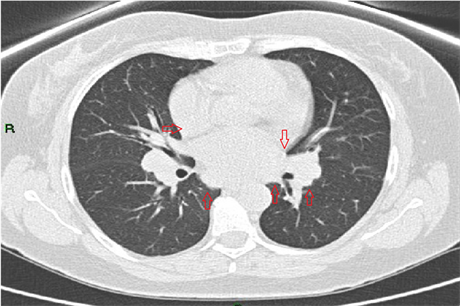

A 58-year-old female who was recently diagnosed with pulmonary Sarcoidosis based on chest CT finding indicated bihilar and mediastinal lymph nodes enlargement (Figure 5―CT scan of the chest showing bihilar and mediastinal

Figure 5. CT scan of the chest showing bihilar and mediastinal lymph nodes enlargement (red arrows).

lymph nodes enlargement (red arrows)) and high level of serum Angiotensin converting enzyme (ACE). The patient brought to emergency room after complaining on prolonged fatigue and dizziness and recurrent episodes of pre-syncope for the last several weeks. Initial 12 leads ECG revealed complete atrioventricular block (Figure 6―12 leads ECG show multiple non-conducted P waves (black arrows) with ventricular escape rhythm indicate complete atrioventricular block). Initial lab results showed modest increase in cardiac enzymes but near normal coronary angiography dismissed ischemic cause. On Electrophysiological study there was no evidence of inducible tachyarrhythmia which eventually lead us to suspect cardiac involvement of Pulmonary Sarcoidosis. Patients was treated by a permanent pacemaker (Figure 7―Chest X-ray image show bihilar lymph nodes enlargement (red arrows) and dual camber pacemaker with leads in right atria & ventricle (red circles)). Follow up revealed no further episodes.